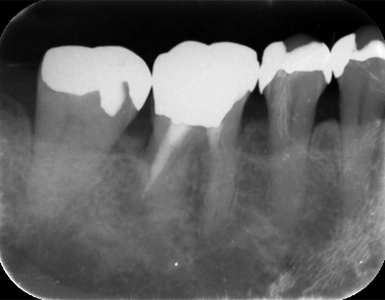

CASE1

歯周組織再生療法(保険診療)

術前

術後(1年後)

年齢・性別 50歳・女性

主訴 市の歯周病健診で歯周病を指摘された

診断名 広汎型慢性歯周炎ステージⅢグレードB

治療内容 歯周基本治療 歯石除去、ブラッシング指導により歯肉の炎症をできる限り改善し、その後歯周ポケットが深く歯槽骨の破壊が大きい部分に対して、歯周外科処置を行った。

治療期間 初診から歯周外科処置まで約5カ月、その後メインテナンス

費用 保険診療にて行う

リスク・副作用 術後の痛み、腫れ、出血が出ることがある

感染の可能性、腫れや再生不良が起こることがある

喫煙や清掃不良、炎症が重度の場合は組織再生の効果が十分得られないことがある

歯肉が引き締まる過程で知覚過敏が起こることがある。